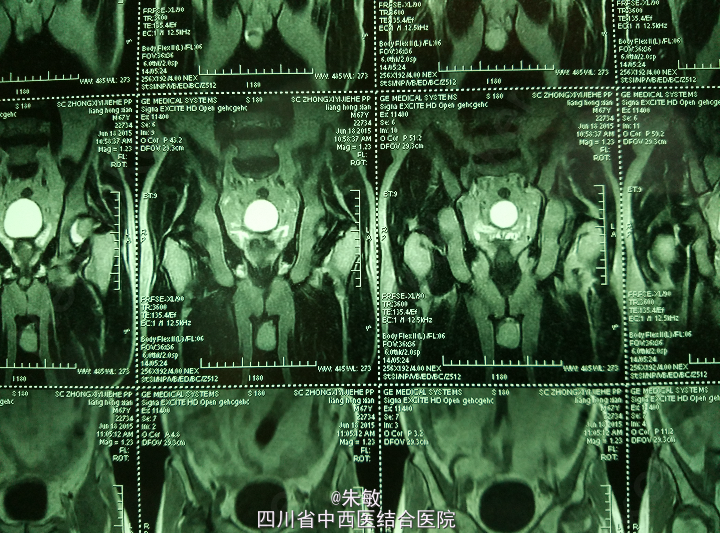

4.本院MRI:左髋关节间隙稍窄,两侧股骨头关节面下斑片、条状异常信号,两侧髋关节囊积液,以左侧明显。关节周围软组织层次清楚,考虑双侧股骨头无菌坏死。

诊断: 双侧股骨头坏死